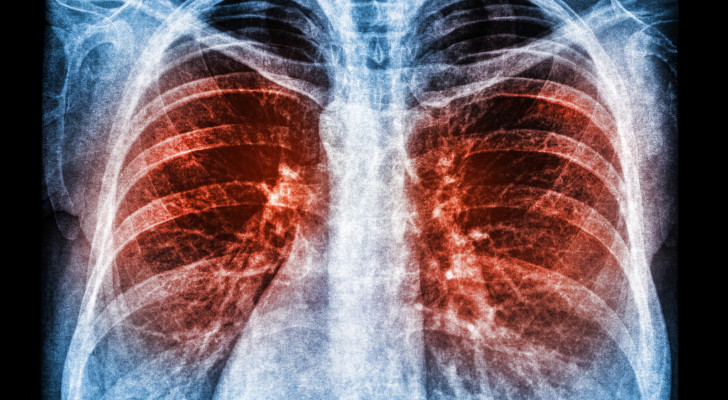

التهاب الصدر

هل تعاني من التهابات متكررة في الصدر في الآونة الأخيرة؟ إليك أهم المعلومات

تكرار التهابات الصدر ليس دائما أمرا عابرا، وقد يكون مؤشرا على حالة تحتاج إلى تشخيص دقيق، خاصة إذا ترافقت مع أعراض مستمرة أو متكررة.

أشعة صدر